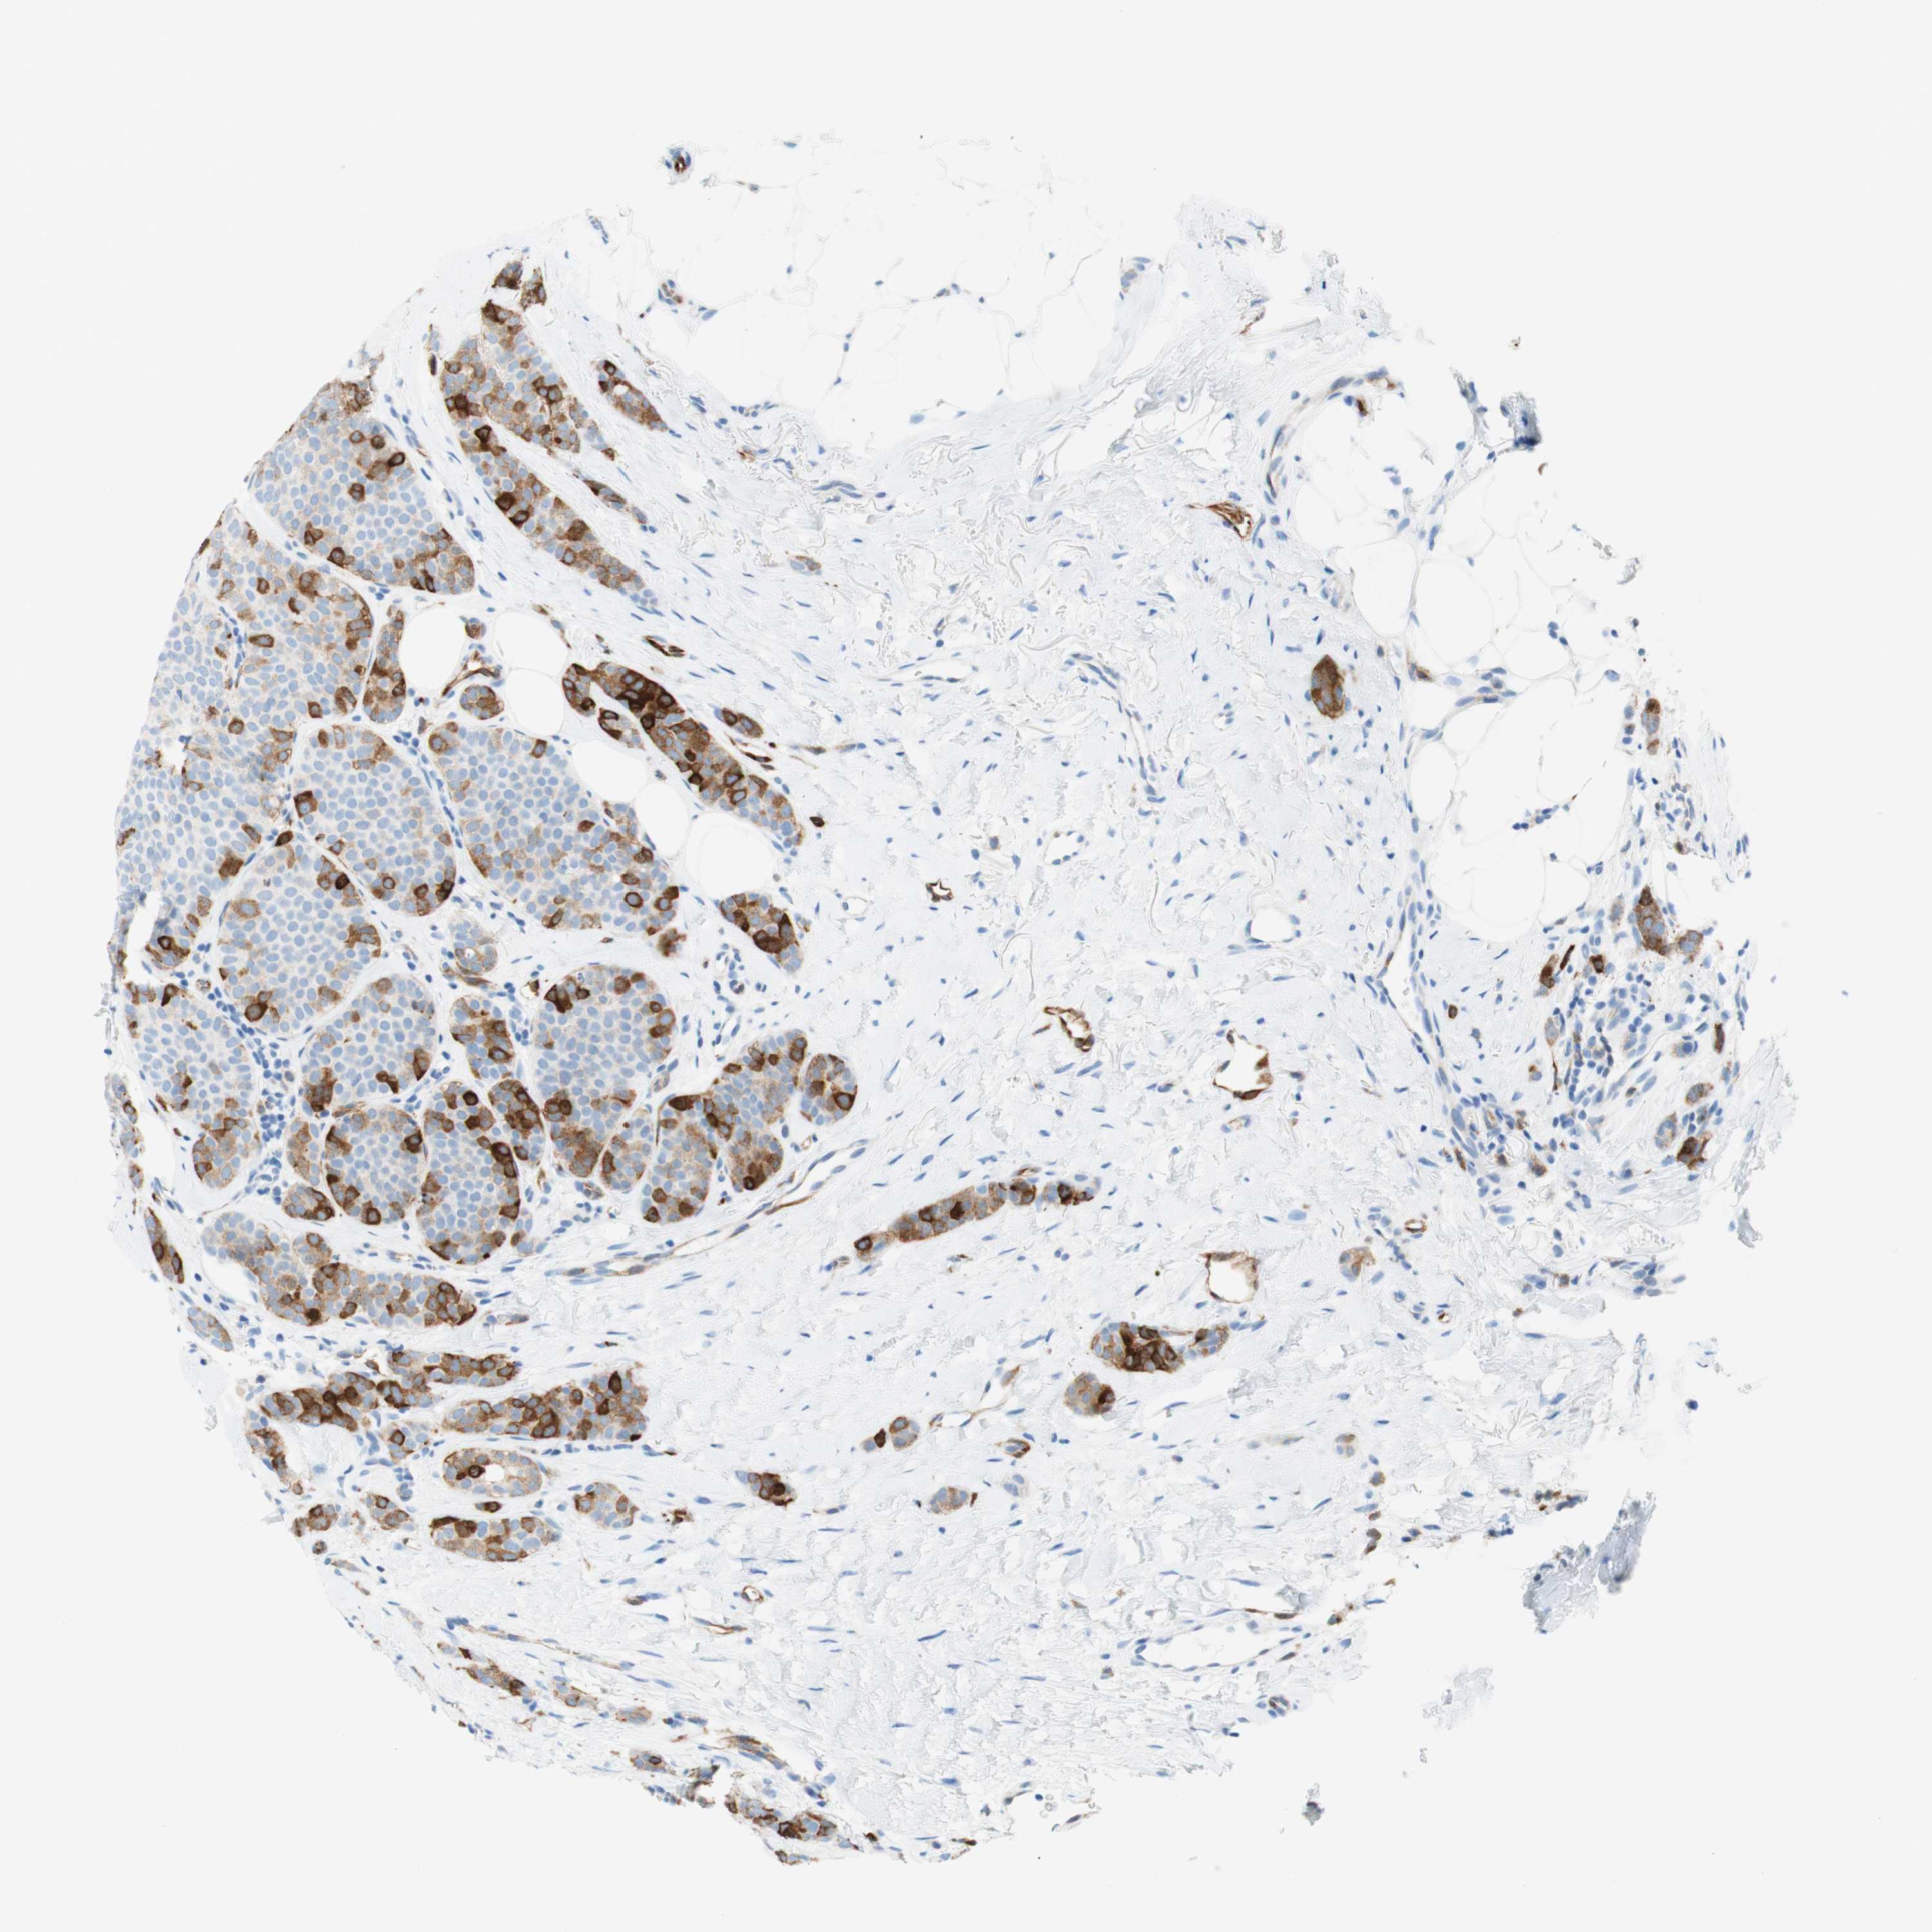

STMN1

CANCER BREAST CANCER Show tissue menu

BRCA TCGA BRCA VALIDATION PROTEIN EXPRESSION

ANTIBODIES

AND

VALIDATION